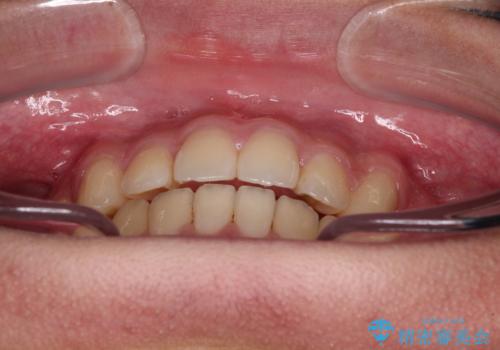

- 前歯のデコボコと隙間を気にして来院された高校生の患者様です。

下顎前歯が上顎前歯を突き上げるような咬み合わせとなっており、その影響で上顎正中に隙間ができている状態でした。

叢生の程度は軽度であり、本人もしっかりと使用する自信があるとのことだったので、インビザラインによる矯正治療を行うこととしました。

突き上げによる隙間を予防する為に、深い咬み合わせを改善するような治療計画としました。咬み合わせを改善させることはできましたが、隙間は後戻りしやすいので、通常の下顎前歯のみではなく、上顎前歯2本もワイヤーで保定を行いました。

高校生ということで、非常に短期間で治療を終えることができました。